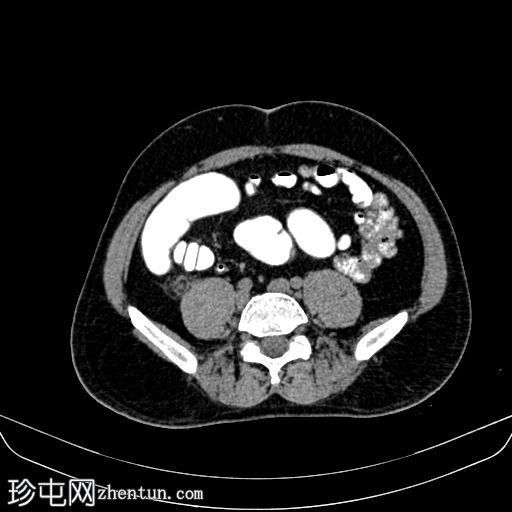

轴位

平扫

平扫CT显示,盲肠后外侧壁旁可见一边界清晰的卵圆形脂肪密度影,周围环绕一薄层高密度环(“高密度环”)。周围脂肪间隙轻度改变,无游离液体,邻近结肠壁未见增厚。动脉期,病灶仍为脂肪密度影,高密度环略有强化;未见动脉出血。